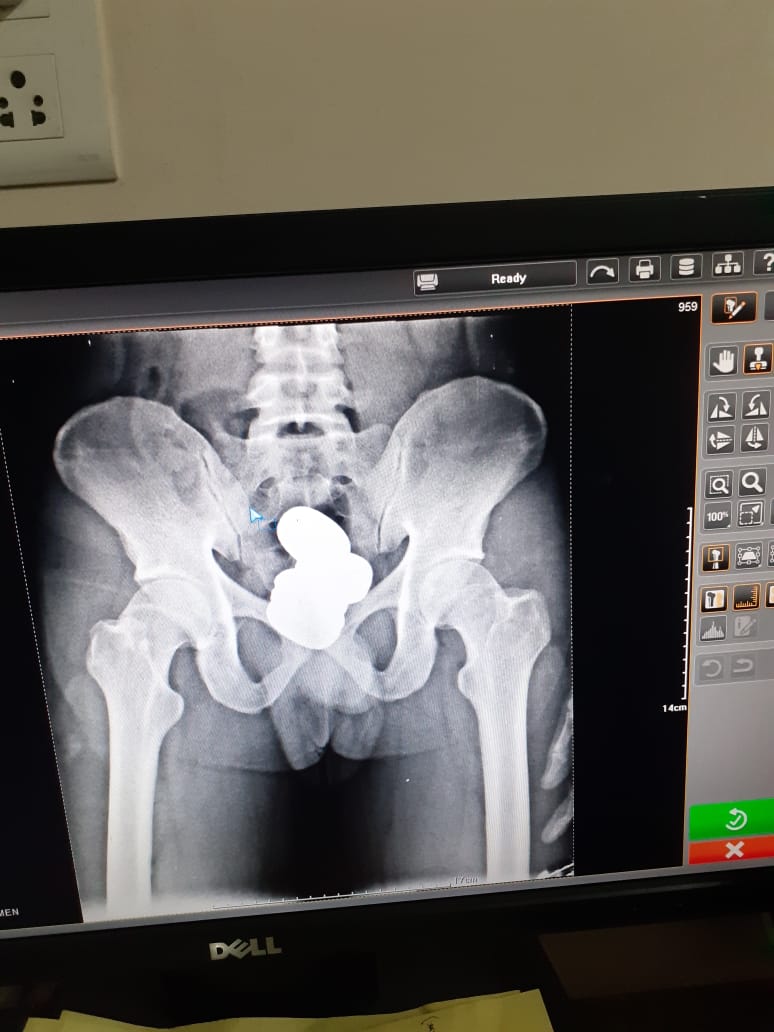

The man was taken to a medical examination room after initial interrogation. An X-ray of his abdomen showed that he was concealing “some metallic items in a body cavity.”

He allegedly confessed to carrying gold in the form of paste inside his rectum, after which the agency recovered four packets of yellow metal paste that weighed about 909.68g. Its value is around Rs 4.2mn (approximately £41,800), the CISF said.